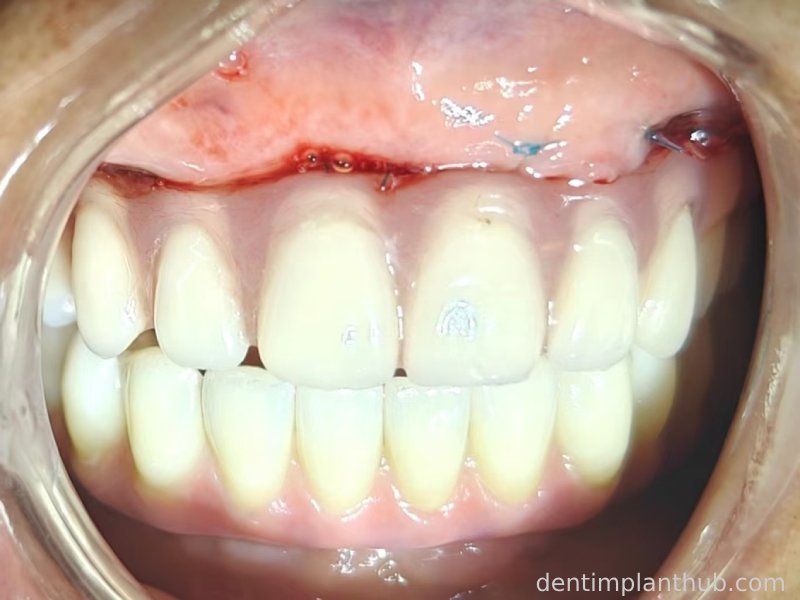

Temporary crown photograph of the upper jaw on 7 June 24

Photo of temporary crown worn into the mouth on the day of surgery, 7 June '24

A fixed prosthesis supported by a Marrowbridge will be worn in the coming months, and the case will be completed at that time.